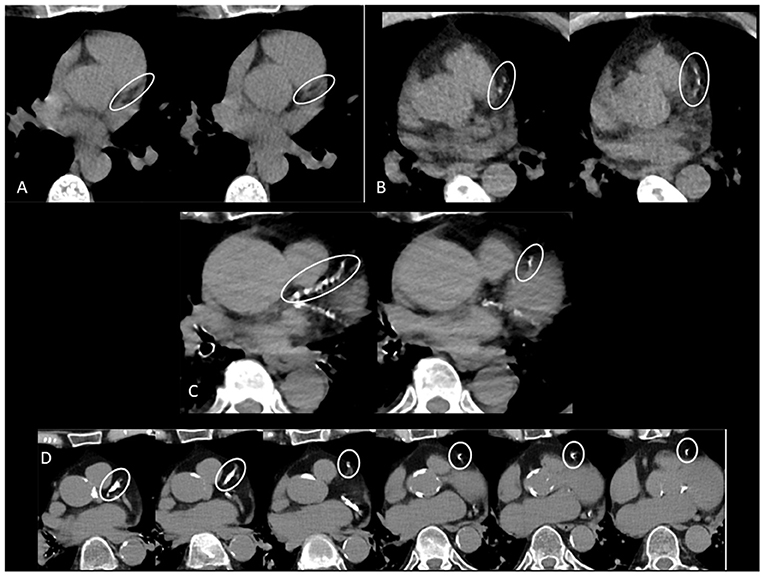

Coronary Artery Calcium Scoring. Examples Of Coronary Artery Calcium

www.researchgate.net

www.researchgate.net